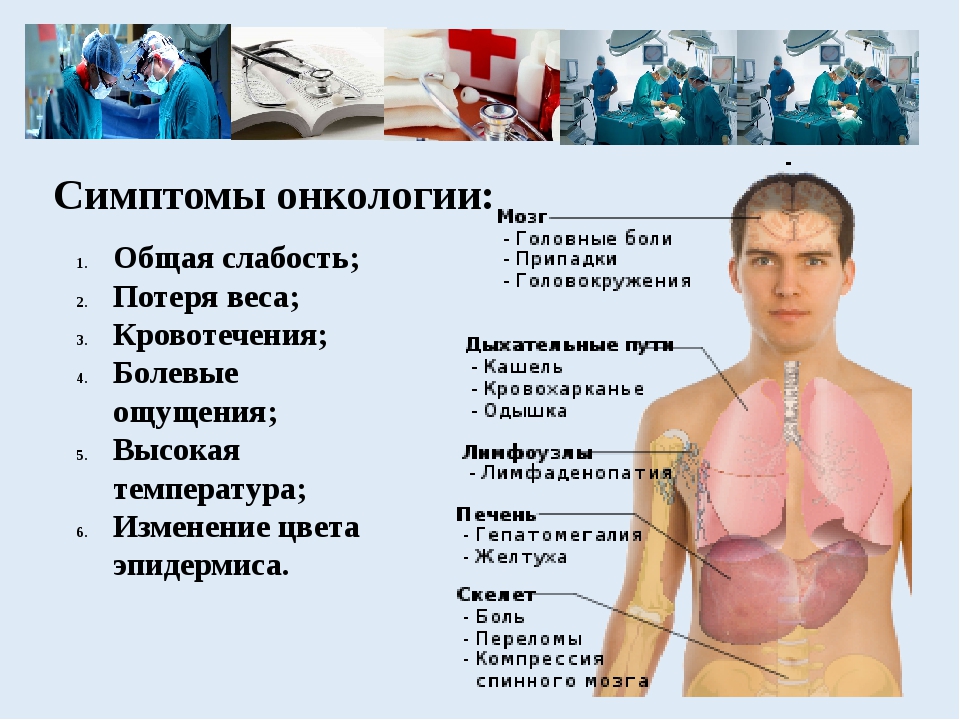

Позитронно-эмиссионная томография мозга. ПЭТ кт головного мозга. ПЭТ кт опухоли головного мозга. Позитронно-эмиссионная томография опухоли. Общие симптомы онкологии. Симптомы онкологических заболеваний. Основные симптомы онкологии. Симптомы раковых заболеваний.

Общие симптомы онкологии. Симптомы онкологических заболеваний. Основные симптомы онкологии. Симптомы раковых заболеваний. НЕЙРОЭКТОДЕРМАЛЬНЫЕ доброкачественные и злокачественные опухоли. Опухоли оболочек мозга. НЕЙРОЭКТОДЕРМАЛЬНЫЕ опухоли головного мозга.